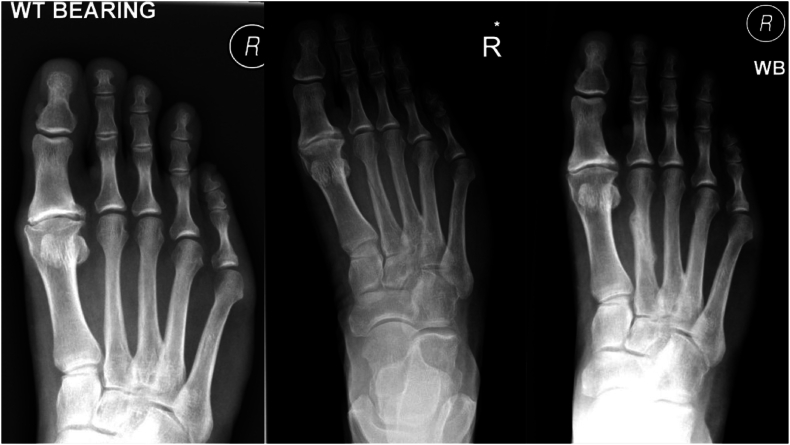

The second to fourth metatarsals are subject to significant forces on weightbearing. Owing to their small cross-sectional area, they are prone to stress fractures (Fig. 2).41 A long second metatarsal relative to the first (Morton's toe) may contribute to second metatarsal stress fractures1; Achilles contracture may contribute to metaphyseal fractures of the second metatarsal. The unique posture adopted by dancers wherein the ankle and foot are placed in extreme plantar flexion whilst weightbearing, results in locking of the metatarsocuneiform joints leading to increased stress at second and third metatarsal bases.40 Pes planus and plantar fascia rupture have been implicated in second and third metatarsal fracture due to an increase in metatarsal strain.1 Variation in sagittal declination of the metatarsals may also contribute to the evolution of stress fractures as increased plantar declination increases the GRF through the metatarsal.

Fig. 2.

Right foot radiographs taken on day 1 of injury, 6 weeks post injury and 5 months post conservative management of a second metatarsal diaphyseal fracture. Note the complete absence of any bony abnormality on the day of injury: hence the need for a high index of suspicion and a review of such patients with these fractures in the athletic population.

These present amongst highly active individuals with vague midfoot pain2 which worsens on activity and tenderness over the affected metatarsals. Plain radiographs may rarely reveal a cortical lucency or fracture with MRI scans most often showing a stress reaction.